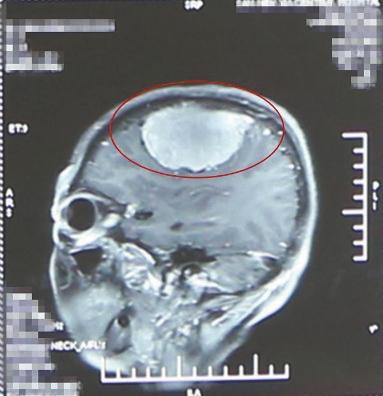

張大娘手術前頭顱CT顯示,腦子裡發現拳頭大的腫瘤

在她大腦硬膜與腦組織間有一個腫瘤,直徑7厘米,足有成人拳頭大!需要趕緊切除!